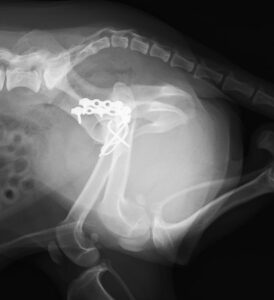

交通事故で当院夜間救急外来へ来院しました。右後肢に重度の疼痛と内出血を認め、X線検査にて複数箇所の「骨盤骨折」が見つかりました。幸い他に大きな致命傷はありませんでしたが、念の為、点滴や痛み止めを使用しながら内科治療を実施し、受傷から3日後に骨盤骨折の整復術を行いました。複雑な場所の骨折だったため、小さいプレートを駆使しながら正しい位置で固定。6週間後には元気に走り回っています。